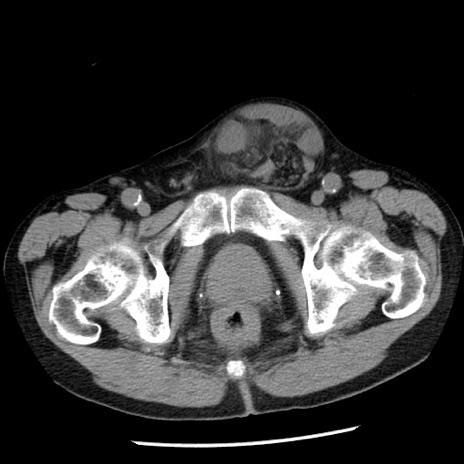

症例26(横断像)

【症例】80歳代男性

【主訴】嘔吐

【現病歴】昨晩2回嘔吐あり、今朝になっても嘔吐あり。来院。

【既往歴】胃潰瘍

【身体所見】意識清明、BT 37.6℃、BP 166/95mmHg、HR 100bpm、SpO2 97%、腹部:平坦・軟、腸蠕動音聴取良好、圧痛なし。

【データ】WBC 21900、CRP 1.46